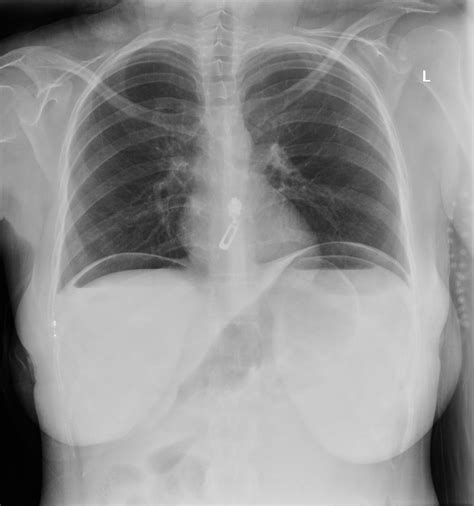

Pneumoperitoneum X-ray

Pneumoperitoneum Chest X-ray

Pneumoperitoneum X-ray Findings

Pneumoperitoneum Chest Radiograph

Air Under Diaphragm CXR

Perforation Chest X-ray

Pneumoperitoneum vs Normal X-ray